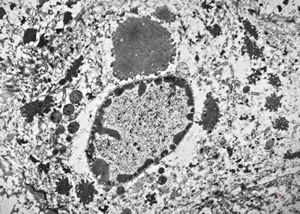

F, 37y. | mycosis fungoides … cerebriform nucleus of Sézary cell